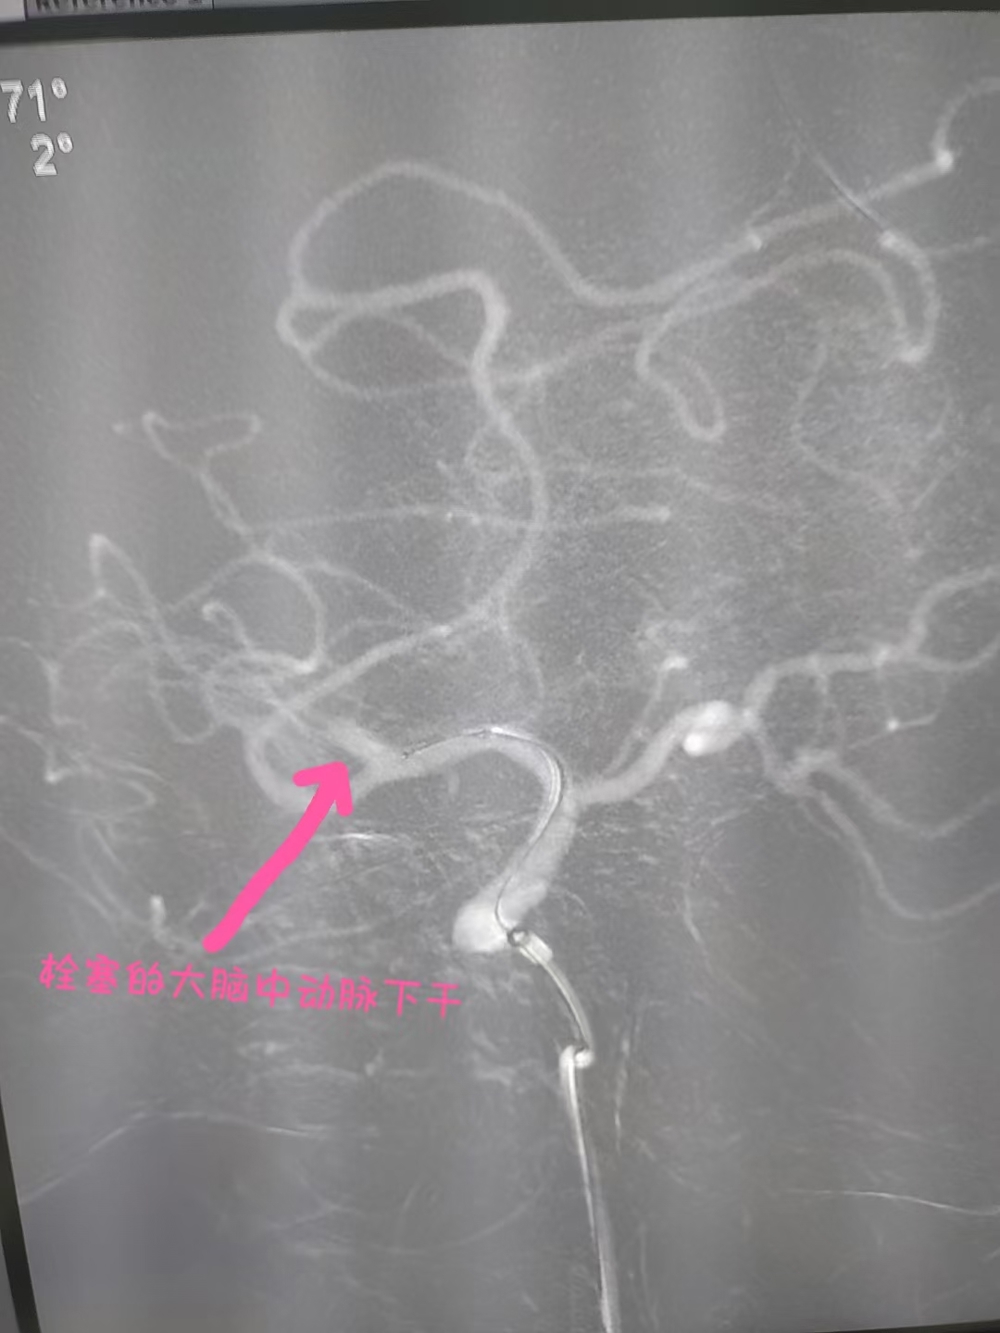

近日,91岁的莫伯伯突发言语不清、左侧肢体瘫痪,家属意识到疾病的危险,这很有可能就是“中风”的表现,马上送至我院急诊科就诊。急诊科医师接诊后考虑脑卒中,立刻为其开通卒中绿色通道,神经内科医师急会诊查看病情,结合头颅MRI检查考虑莫伯伯右侧大脑中动脉下干栓塞,右侧大脑半球梗死。立即通知神经内科主任、副主任医师胡华林指导治疗。胡华林主任会诊后将脑血管取栓手术的必要性与风险详细告知家属,征得同意后急诊进行手术治疗。

术后大脑中动脉再通

胡华林主任及其介入团队快速制定手术方案。行脑血管造影示:III型主动脉弓右侧大脑中动脉下干栓塞,通过介入取栓55分钟开通了闭塞的右侧大脑中动脉,莫伯伯的右侧大脑中动脉成功恢复了血流再通。手术非常顺利,莫伯伯术后言语恢复清晰,能够自由下床活动,日常生活能自理。胡华林主任针对莫伯伯基础疾病及时调整用药,并叮嘱规律服药和返院复查等相关事宜,术后1周后莫伯伯顺利出院。